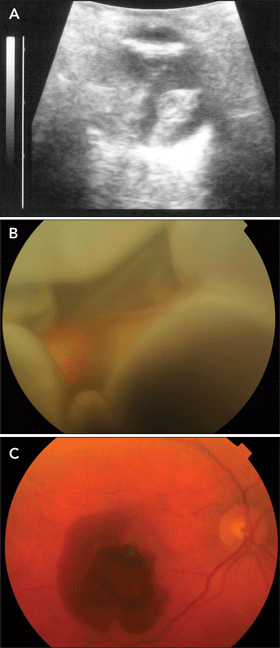

B-mode ultrasonography and dilated fundus examination revealed massive suprachoroidal haemorrhage (Figures A and B). The INR was 6.0, which was reversed with intravenous administration of two units of fresh frozen plasma and 1 mg of vitamin K. Visual acuity in the patient’s left eye deteriorated to light perception. As there were no signs of spontaneous improvement and this had been his better eye, surgery was performed to drain the haemorrhage. After surgery, the haemorrhage decreased in size but his vision did not improve.

An 82-year-old man presented with a 3-week history of a shadow in his left eye. He had been taking low-dose aspirin for ischaemic heart disease and stroke, but had no known ocular history. On examination, visual acuity was 6/5 and hand movements in his right and left eye, respectively, and massive subretinal haemorrhage was noted in the left eye. Non-neovascular AMD was present in his right eye, and the haemorrhage in his left eye was presumed to be due to a combination of neovascular AMD and the effects of aspirin. He was offered surgery, but declined as there was little chance of improvement in central vision. Subsequently, he gradually lost all vision (including light perception) in his left eye. Aspirin was continued because of his significant cardiovascular history. Over the following year, neovascular AMD developed in his right eye and visual acuity dropped from 6/5 to 6/36 (Figure C). He was treated with regular intravitreal ranibizumab injections, and his vision stabilised.

However, several months later, vision in his right eye suddenly deteriorated to vague perception of light. On examination of his right eye, there was no view of the fundus due to a dense cataract and vitreous haemorrhage, but B-mode ultrasonography once again revealed massive choroidal, subretinal and vitreous haemorrhage. The patient was still taking low-dose aspirin therapy, which was subsequently ceased. In an attempt to preserve vision in his only seeing eye, he underwent vitrectomy and silicone oil insertion, but there was no improvement and he subsequently lost light perception in his right eye.

A: B-mode ultrasonogram of Patient 1’s left eye, showing massive suprachoroidal haemorrhage. B: Fundus photograph of Patient 1’s left eye, showing massive suprachoroidal haemorrhage bulging forward (therefore largely out of focus). C: Fundus photograph of Patient 2’s right eye, showing right neovascular AMD with subretinal haemorrhage, prior to development of massive suprachoroidal, subretinal and vitreous haemorrhage.